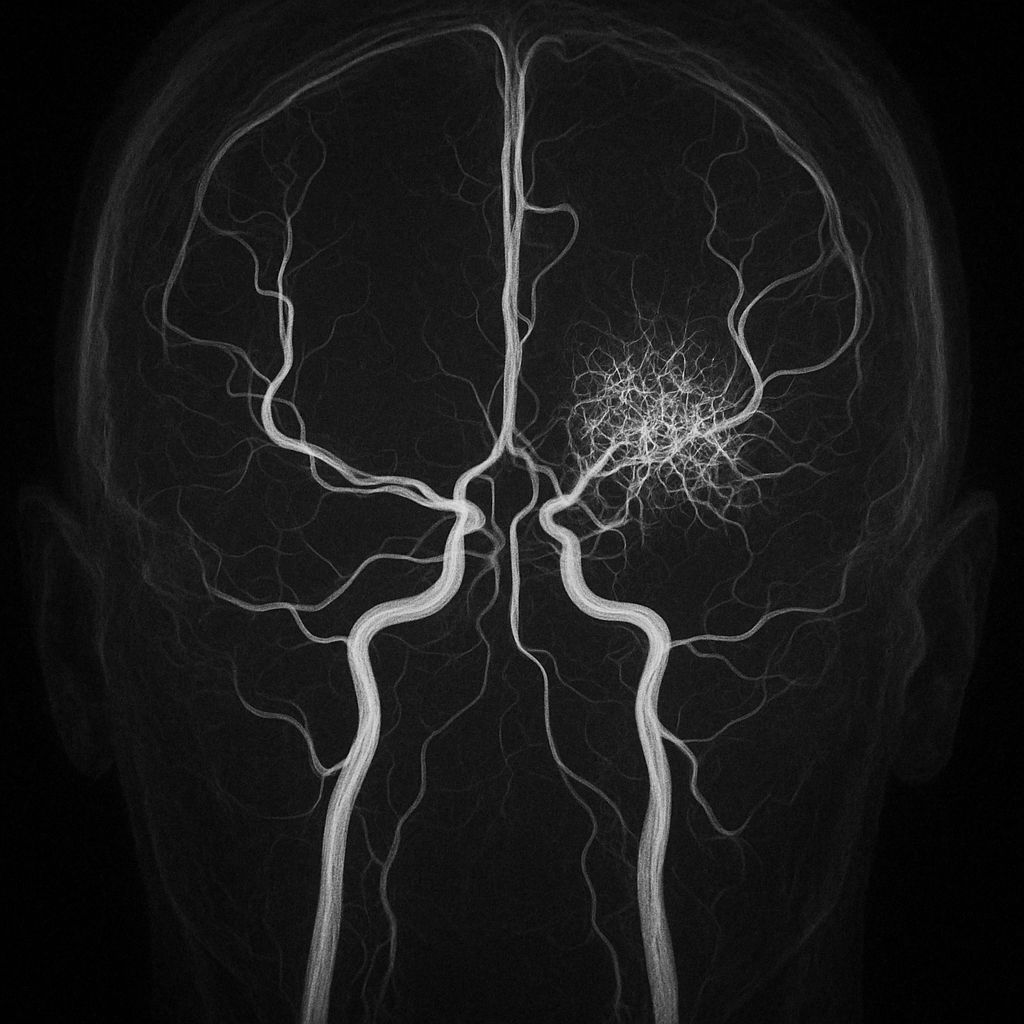

• Diagnosis is clinical, supported by characteristic MRI findings of large, bilateral, asymmetric T2/FLAIR hyperintense lesions without mass effect.

• Lesions are poorly demarcated, often involve both gray and white matter, and rarely show gadolinium enhancement.